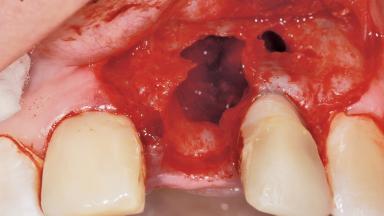

Early Placement of an Implant in a Maxillary Right Central Incisor Site

This 41-year-old female patient was referred to the clinic for the replacement of the right central incisor, since the tooth had developed a root fracture in the long axis that made extraction necessary. The healthy, non-smoking patient was first seen with the tooth still in place. A detailed Esthetic Risk Assessment was performed.The patient was worried about her dental esthetics and had high expectations for a successful treatment outcome from an esthetic point of view. The patient had a medium lip line that displayed parts of the gingiva in the anterior maxilla upon smile.

Bone Volume Deficient horizontally, allowing simultaneous augumentation